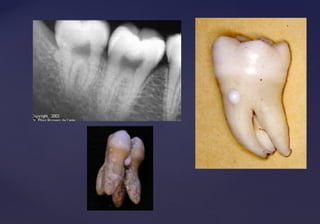

TAURODONCIATAURODONCIA

 Molar con una corona alargada y situada enMolar con una corona alargada y situada en

posición apical respecto a la bifurcación de lasposición apical respecto a la bifurcación de las

raíces que da por resultado una cámara pulparraíces que da por resultado una cámara pulpar

coronal rectangular de tamaño mayor que elcoronal rectangular de tamaño mayor que el

normal.normal.

 Causada por la desorganización de los tejidosCausada por la desorganización de los tejidos

descalcificados.descalcificados.

 Fuerzas excesivas durante la masticación.Fuerzas excesivas durante la masticación.

 Afecta los molares, ocasionalmente losAfecta los molares, ocasionalmente los

premolares.premolares.

 Afecta dientes permanentes y deciduos.Afecta dientes permanentes y deciduos.

DENS IN DENTEDENS IN DENTE::

 Invaginación de las células delInvaginación de las células del

epitelio interno del órgano delepitelio interno del órgano del

esmalte, por enclavamientoesmalte, por enclavamiento

del ectodermo hacia la papiladel ectodermo hacia la papila

dentaldental

 El esmalte que cubre la superficieEl esmalte que cubre la superficie

de la cavidad da la apariencia dede la cavidad da la apariencia de

un diente que contiene otroun diente que contiene otro

pequeño en su interior.pequeño en su interior.

 Causas: Aumento de la presión externa,

trauma, estimulación del crecimiento focal en

ciertas áreas de la papila dentaria

Dens in Dente

Anomalía del desarrollo, durante la cual se produce una exageración en laAnomalía del desarrollo, durante la cual se produce una exageración en la

profundización de la fosa palatina de incisivos centrales, laterales o caninos.profundización de la fosa palatina de incisivos centrales, laterales o caninos.

Hendidura en el epitelio del esmalte por lo que aparece una fosa exagerada yHendidura en el epitelio del esmalte por lo que aparece una fosa exagerada y

cubierta por esmalte, dando el aspecto radiográfico de un diente dentro de otrocubierta por esmalte, dando el aspecto radiográfico de un diente dentro de otro

diente.diente.